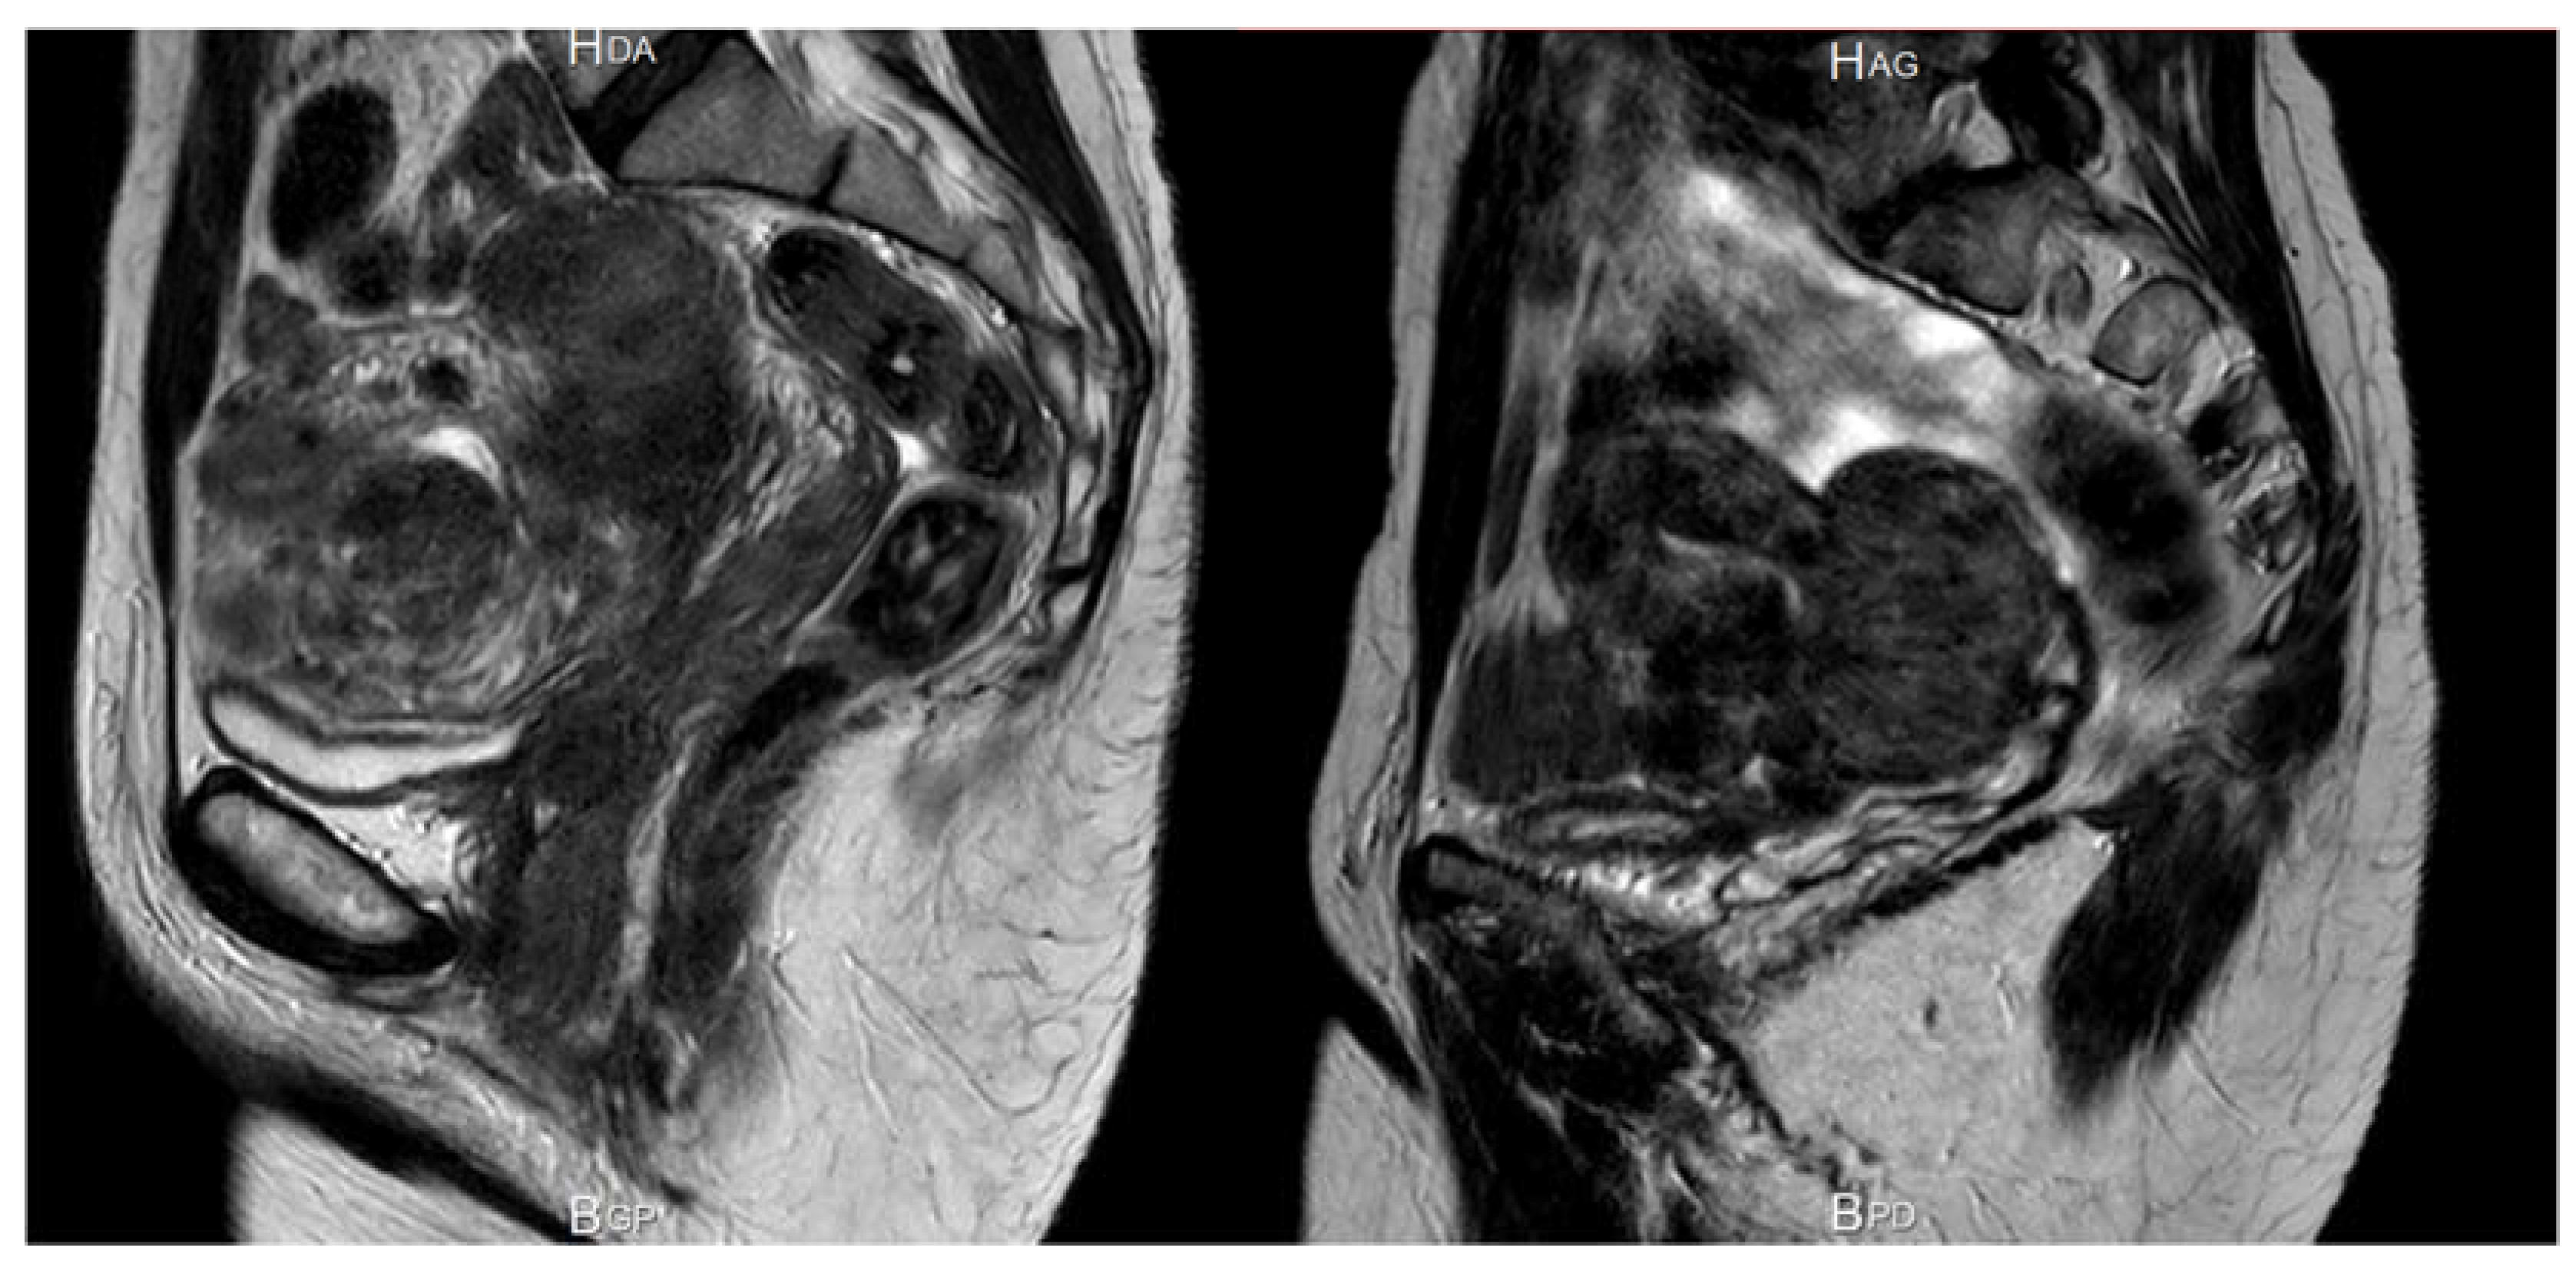

2.3. Uterine Venous Ectasia by Compression from the Myoma